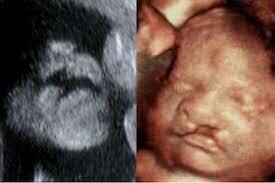

• 4D Tech.

4D Tech.

the adoption of 4D (real time) capabilities. Ultrasound guided biopsies (endoscopic ultrasounds) also began in the 1990s. Similar to a 3D ultrasound, except it displays the images of the baby in a live-streaming video.